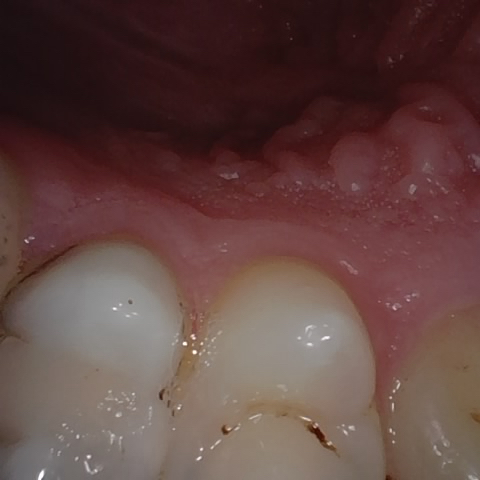

Annotated as "Good"

Original Image Rendering Image